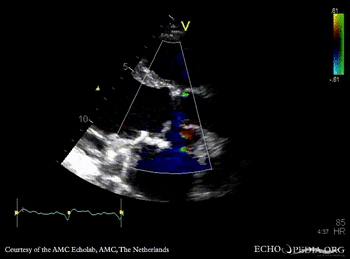

Abscess of aortic valve prosthesis

PSAX: mechanical aortic valve prosthesis, abscess cavity PSAX with Color Doppler